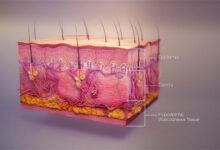

محور الاعجاز في علم التشريح والوظائف

تحميل محور الاعجاز في علم التشريح والوظائف